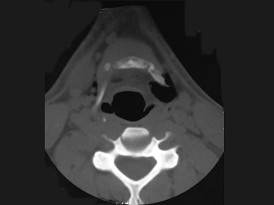

11.27歲男性,開車外出在高速行駛時翻車,呼吸困難,喉部腫脹,CT檢查如圖所示,請選擇正確的描述或診斷  (    )

正確答案:ABCE